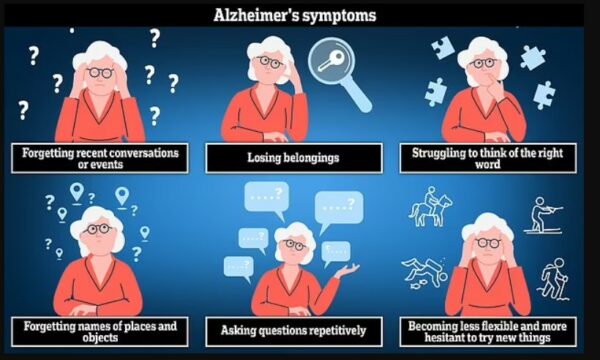

Testi 60-sekondësh i të shkruarit që mund të zbulojë shenjat më të hershme të dementias

Testi 60-sekondësh i të shkruarit që mund të zbulojë shenjat më të hershme të dementias